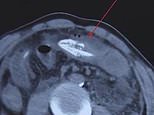

A Chinese man nearly died after allegedly inserting a wiggling 16-inch eel into his backside to treat his constipation. The picture shows an X-ray scan of the patient in southern China

Dr Li from the hospital told the local media: ‘[We] suspected that there was a foreign object in his abdominal cavity from a CT scan. But we couldn’t tell where it came from.’